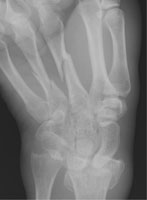

- Click on the image for a larger versionAScaphoid deviated radiograph of the wrist. This view shows fractures of metacarpals three and four and an impacted fracture of the distal radius.